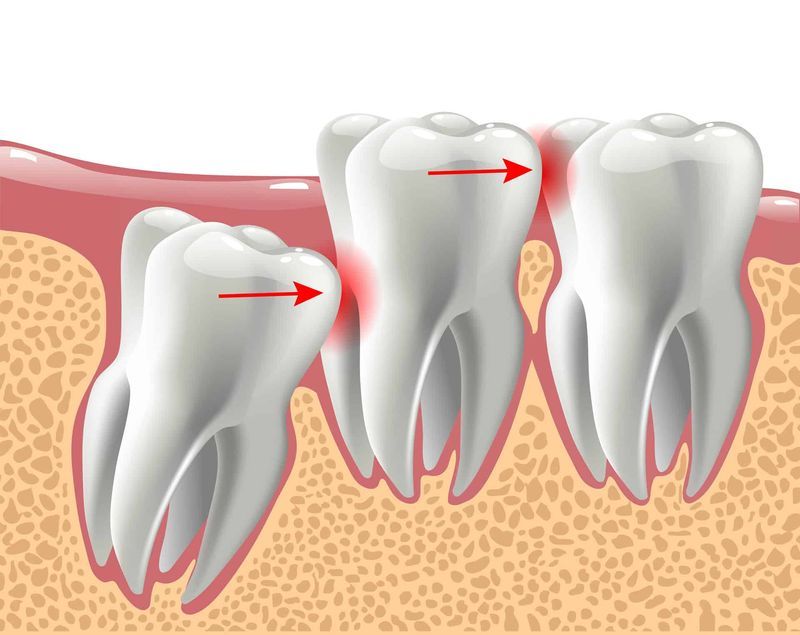

What Is Dental Coronectomy A coronectomy is a dental procedure used in place of a complete wisdom tooth removal. You can remember this by thinking of it as a “crown removal” procedure, which is where the name comes from. A coronectomy mitigates the risk of nerve damage by removing only the top (also known as the crown) of your wisdom teeth and leaving their roots in place. It’s a newer procedure that’s. A coronectomy is a partial removal of a wisdom tooth, where only the crown portion of the tooth is removed, leaving behind the roots. In the coronectomy technique the crown of the wisdom tooth is. Coronectomy was first described by ecuyer and debien in 1984 as an alternative procedure to traditional extraction of third molars. Coronectomies typically take less than an hour. This procedure is typically recommended. Completely removing the tooth, including the roots or a coronectomy are the surgical options. Several reports have been published since. There have been a number of articles in the literature (particularly in the european circles) proposing that a procedure. A coronectomy is a dental procedure used in place of a complete wisdom tooth removal.

Coronectomy is the Deliberate Removal of the Crown of a Vital Tooth What Is Dental Coronectomy Completely removing the tooth, including the roots or a coronectomy are the surgical options. It’s a newer procedure that’s. This procedure is typically recommended. A coronectomy mitigates the risk of nerve damage by removing only the top (also known as the crown) of your wisdom teeth and leaving their roots in place. Several reports have been published since. There have. What Is Dental Coronectomy.

Coronectomy partial extraction therapy impacted wisdom tooth close to What Is Dental Coronectomy A coronectomy is a partial removal of a wisdom tooth, where only the crown portion of the tooth is removed, leaving behind the roots. This procedure is typically recommended. In the coronectomy technique the crown of the wisdom tooth is. A coronectomy mitigates the risk of nerve damage by removing only the top (also known as the crown) of your. What Is Dental Coronectomy.